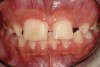

A 9-year-old girl, referred to a prosthodontic office by her pediatric dentist, presented with her mother’s chief complaint: “The kids are teasing her about her big front tooth.” Findings from radiographic and clinical examinations revealed fused maxillary central-peg lateral incisors, teeth Nos. 7 and 8, and a congenitally missing lateral incisor, tooth No. 10 (Figure 1 through Figure 3). An implant was selected as the ideal treatment to replace tooth No. 10 when somatic growth was complete. A diagnostic wax-up was fabricated to determine if the fused tooth could be made to resemble two teeth, using pink composite to give the illusion of an interproximal papilla. The patient was referred for an orthodontic consultation to plan for closure of the diastema between teeth Nos. 8 and 9 and achievement of proper alignment for implant No. 10. The patient was also referred to a periodontist for pretreatment assessment of the tooth No. 10 site. An endodontist was consulted should exposure of the large pulp occur during tooth preparation.

Fig 1 and Fig 2. Pretreatment photographs. Patient at 9 years of age on presentation.